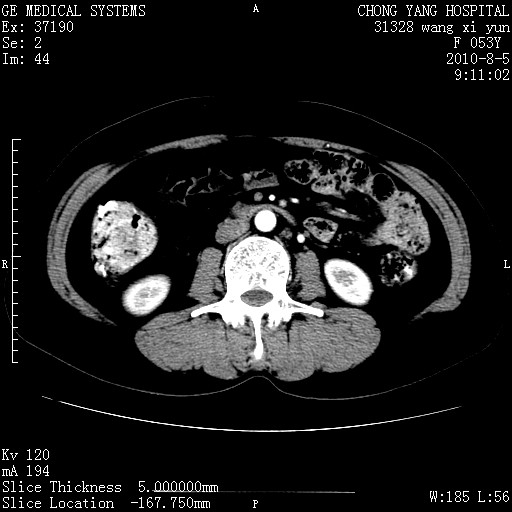

标题: CT28214:F41Y 血尿二十天,建议盆腔平扫加增强。

1)考虑肝左叶胆管细胞癌。2)脂肪肝。